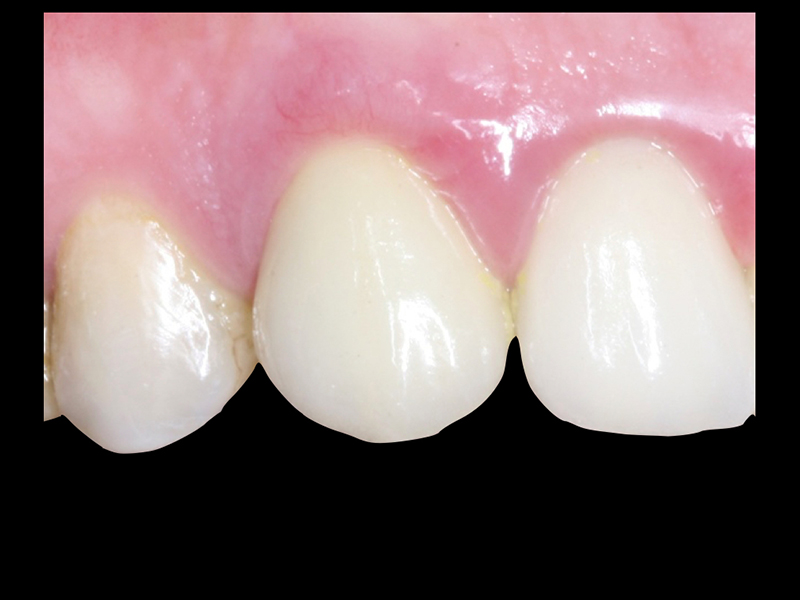

- Conforto e Estética: A prótese provisória é funcional e visualmente semelhante aos dentes naturais.